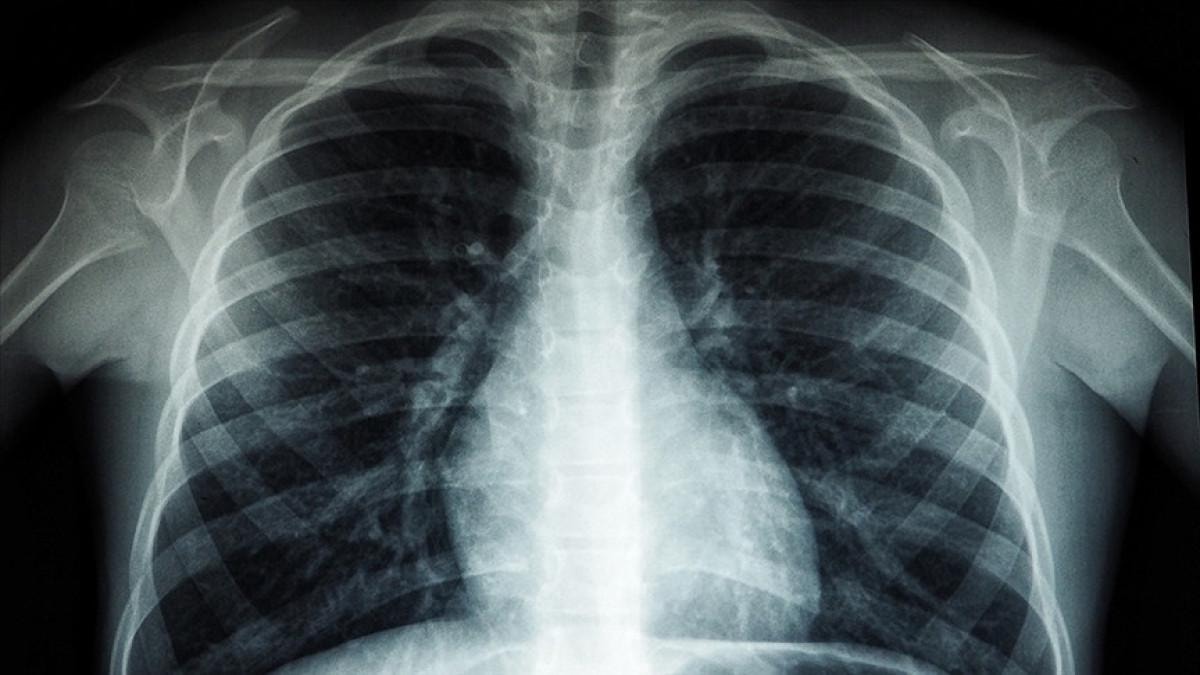

TÜBERKÜLOZ NEDİR?

Tüberküloz (TB) çoğunlukla akciğerleri etkileyen bakterilerin neden olduğu bulaşıcı bir hastalık. Tüberküloz hastaları öksürdüğünde, hapşırdığında veya tükürdüğünde hava yoluyla yayılır.

Dünya Sağlık Örgütü'ne göre tüberküloz önlenebilir ve tedavi edilebilir bir hastalık.